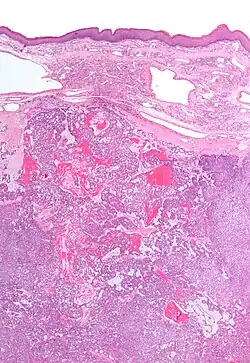

Low magnification micrograph of a polymorphous low-grade adenocarcinoma, showing the typical variation of architectural arrangement. H&E stain. | |

PLGAs consist of a monomorphous cell population that has a varied histologic morphology.

Microscopically, its histology can be confused with an adenoid cystic carcinoma and a pleomorphic adenoma.